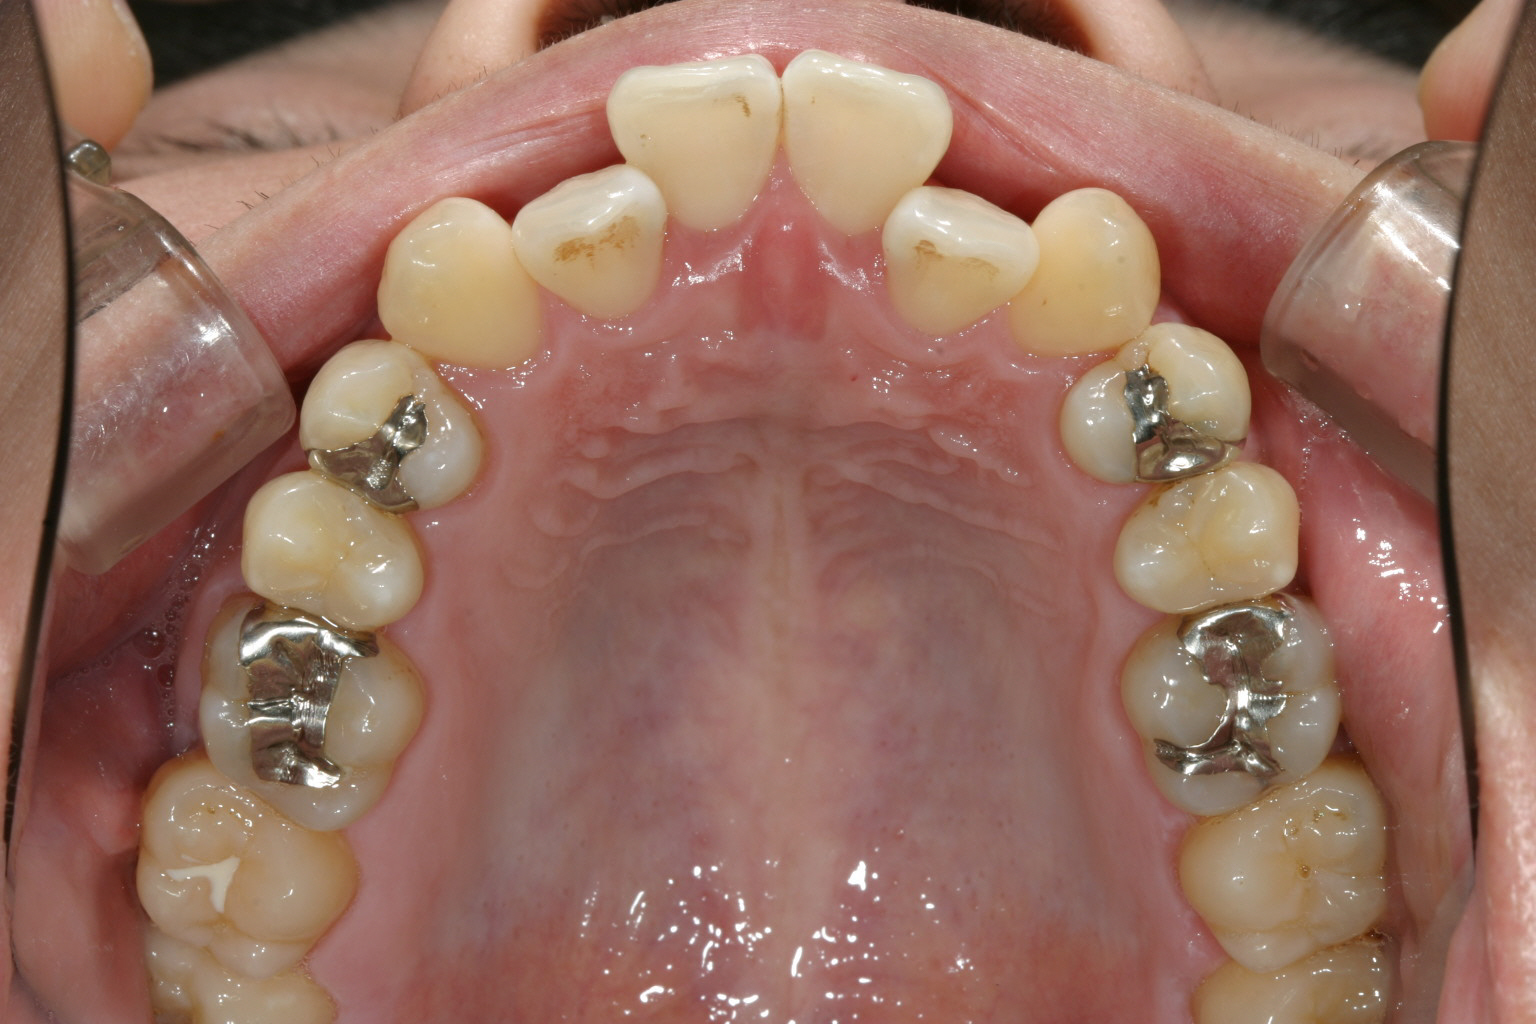

前歯がすご出て又犬歯も飛び出しています。

下顎もアーチが狭い為にガタガタしています。

半年後です。右側の2番目の歯の叢生がだいぶ取れてきました。

下顎もかなり綺麗になって来ましたが左下1番の歯の回転で手こずっています。